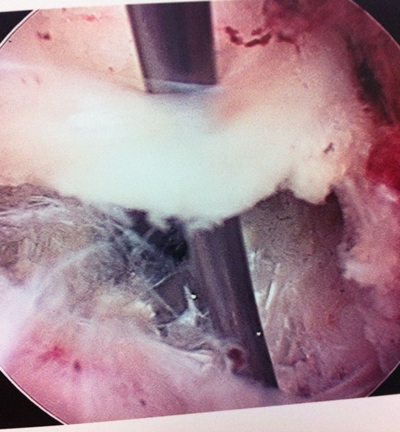

(图)术中

(图)取出的游离髓核